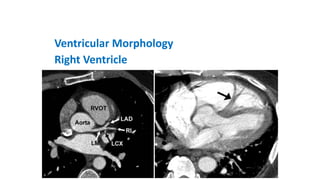

Ventricular Morphology

Right Ventricle